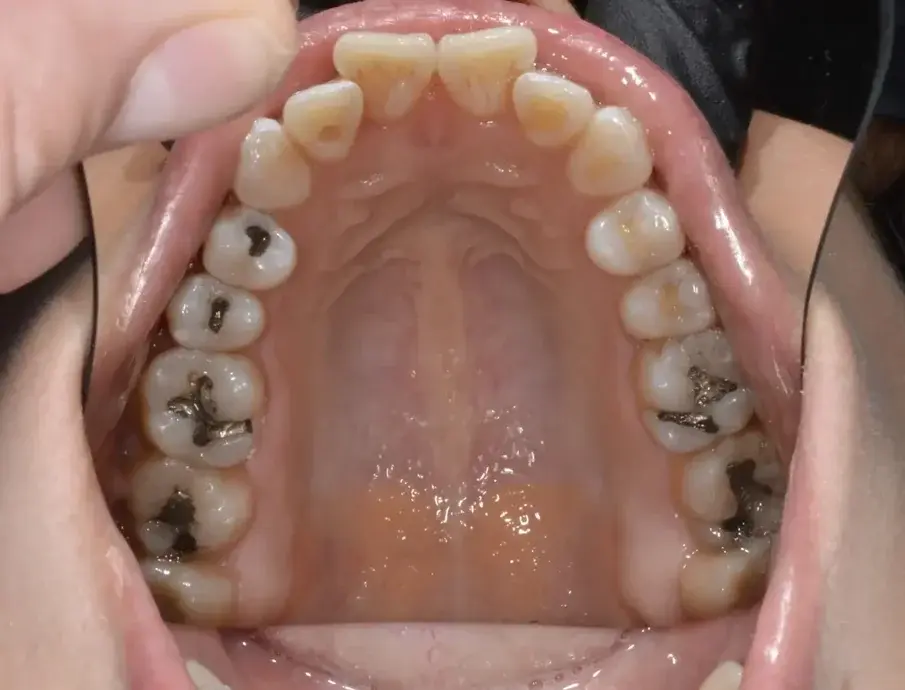

Фиг. 3а: Първоначални оклузални изображения.

Фиг. 3b: Първоначални оклузални изображения.

Фиг. 3c: Първоначални оклузални изображения.

35-годишна пациентка постъпва със струпване на зъби, болки в мускулите и ставите и главоболие след събуждане. При прегледа се установява I скелетен клас със струпване и бимаксиларна протрузия. Изследването на лицето показа конвексен профил с изпъкнали устни и квадратна форма на лицето, която се засилва при усмивка (фиг. 1-4). Тя съобщава за бруксизъм и се наблюдава двустранна хипертрофия на масетерите, но няма изменения в темпоромандибуларните стави.